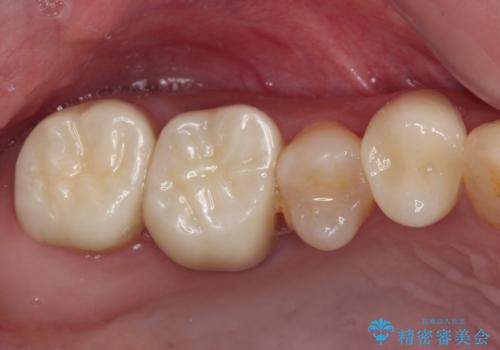

むし歯だらけの奥歯 セラミッククラウンによるむし歯治療

根管治療や歯周外科処置後にフルジルコニアクラウンにて補綴治療することとしました。

再発や他の歯がむし歯となるリスクを低減させるため、日頃からのプラークコントロールと定期的なクリーニングが重要となります。